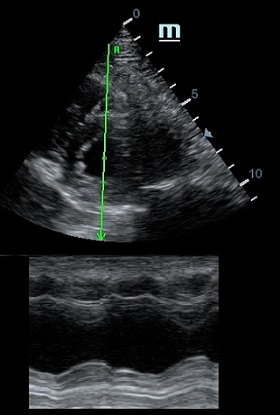

Но как же провести стандартные измерения в М-режиме, если мы его не использовали? На помощь приходит функция Free Xros M – анатомический М-режим. Имея записанную в память прибора видео петлю, мы можем провести линию М-режима в любом месте, при этом корректируя изначально не оптимальный угол.

Возможности применения функции многогранны: от измерения толщины стенок левого желудочка, движения створок митрального клапана и кооптации нижней полой вены до оценки сократимости миокарда как глобально, так и по сегментам.

Оценка сокращения сегментов левого желудочка на глаз постепенно уходит в прошлое. Если в приборе нет функции радиального или лонгитудинального стрейна, на помощь опять может прийти Free Xros. Утолщение более 5 мм в систолу – нормальное сокращение, 2-5 мм гипокинез, истончение в систолу – дискинез.